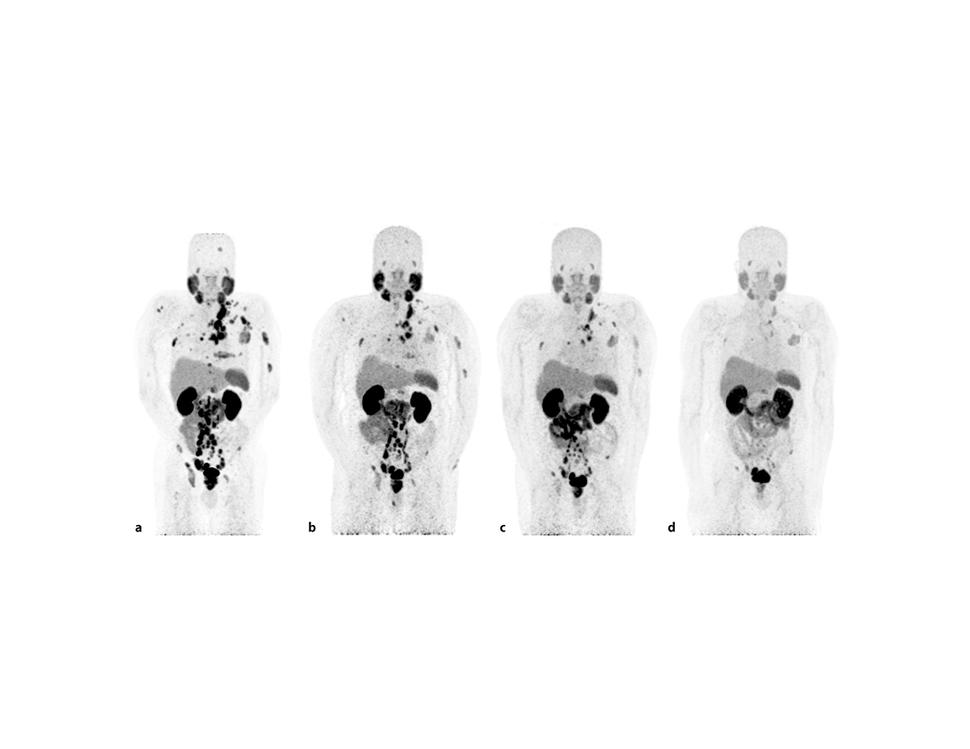

Serie de tomografía por emisión de positrones que muestran menos tumores después del tratamiento con Lu177-PSMA-617

Tomografía por emisión de positrones (TEP) del antígeno prostático específico de membrana (PSMA) de un hombre con cáncer de próstata (a) al inicio del tratamiento con Lu177-PSMA-617 y (d) después de 6 ciclos de la terapia.

Fuente: Tijdschrift voor Urologie. Agosto 2020. https://doi.org/10.1007/s13629-020-00300-z. CC-BY-4.0